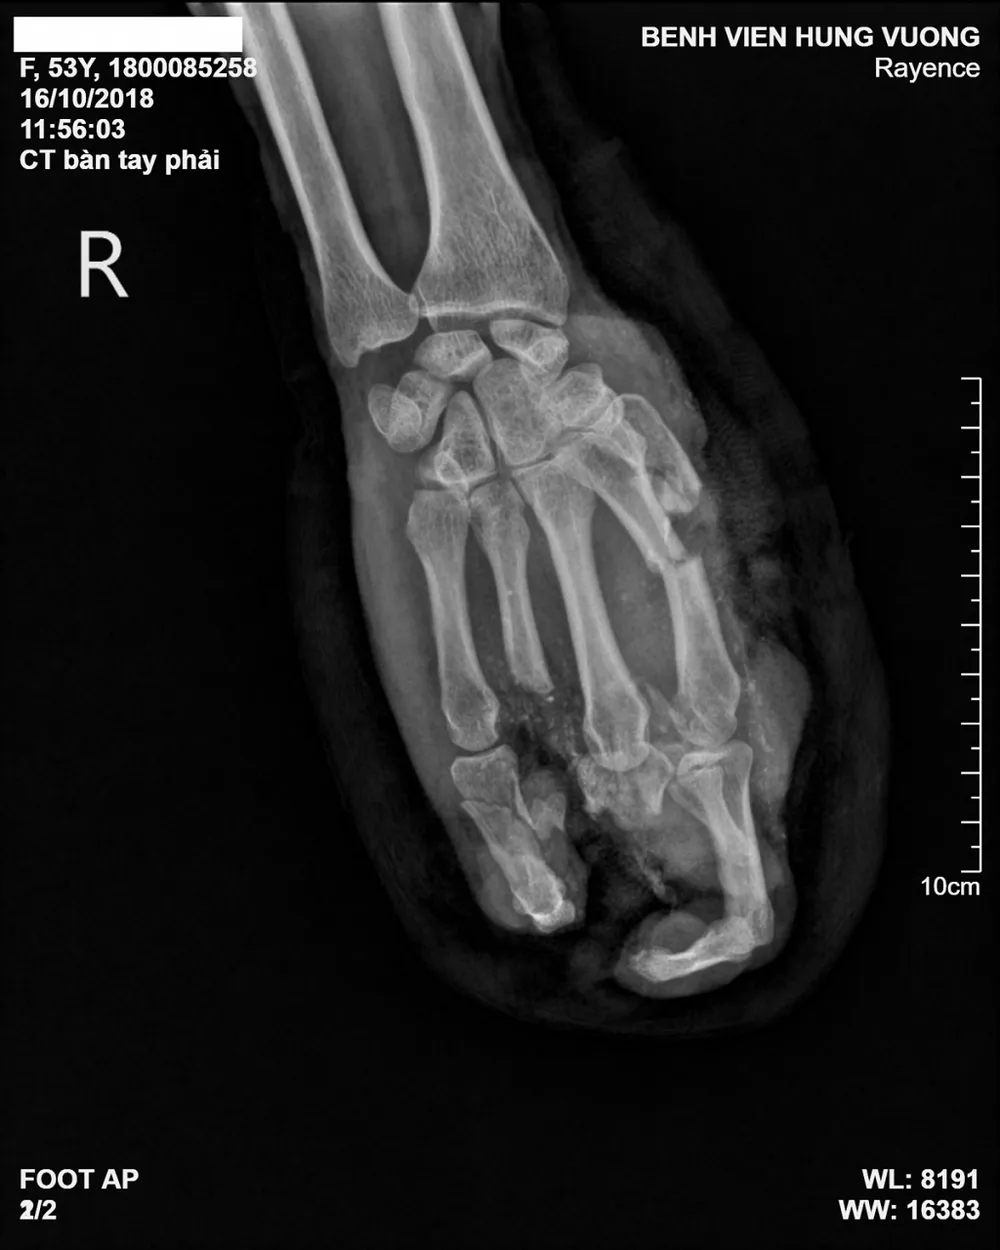

Ngay lập tức bệnh nhân được vệ sinh vết thương và cầm máu. Kết quả chụp X-quang bàn tay phải cho thấy bệnh nhân bị gãy cụt phức tạp các xương bàn, ngón tay phải.

Ảnh chụp X-quang bàn tay của bệnh nhân